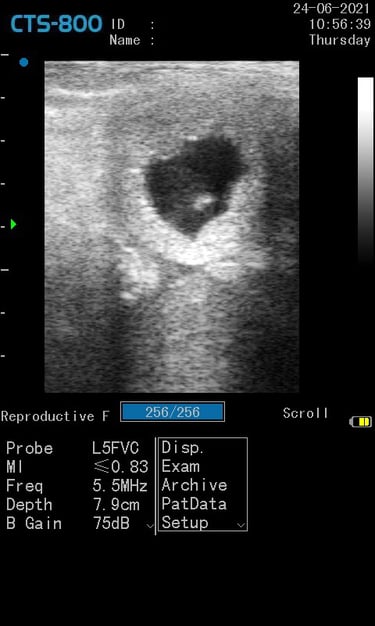

Gynécologie